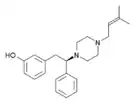

The pharmacodynamic response to an opioid depends upon the receptor to which it binds, its affinity for that receptor, and whether the opioid is an agonist or an antagonist. For example, the supraspinal analgesic properties of the opioid agonist morphine are mediated by activation of the μ1 receptor; respiratory depression and physical dependence by the μ2 receptor; and sedation and spinal analgesia by the κ receptor. Each group of opioid receptors elicits a distinct set of neurological responses, with the receptor subtypes (such as μ1 and μ2 for example) providing even more [measurably] specific responses. Unique to each opioid is its distinct binding affinity to the various classes of opioid receptors (e.g. the μ, κ, and δ opioid receptors are activated at different magnitudes according to the specific receptor binding affinities of the opioid). For example, the opiate alkaloid morphine exhibits high-affinity binding to the μ-opioid receptor, while ketazocine exhibits high affinity to ĸ receptors. It is this combinatorial mechanism that allows for such a wide class of opioids and molecular designs to exist, each with its own unique effect profile. Their individual molecular structure is also responsible for their different duration of action, whereby metabolic breakdown (such as N-dealkylation) is responsible for opioid metabolism.

Opioid comparison